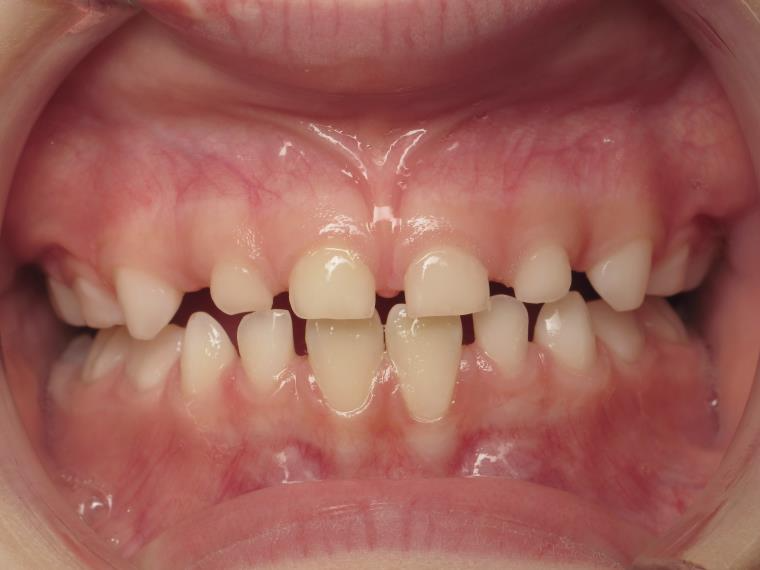

12 béance inversé droit 4 ans

inversion postérieur coté droit et espace entre les dents du haut et du bas (diastèmes)

bilan début et en cours de traitement